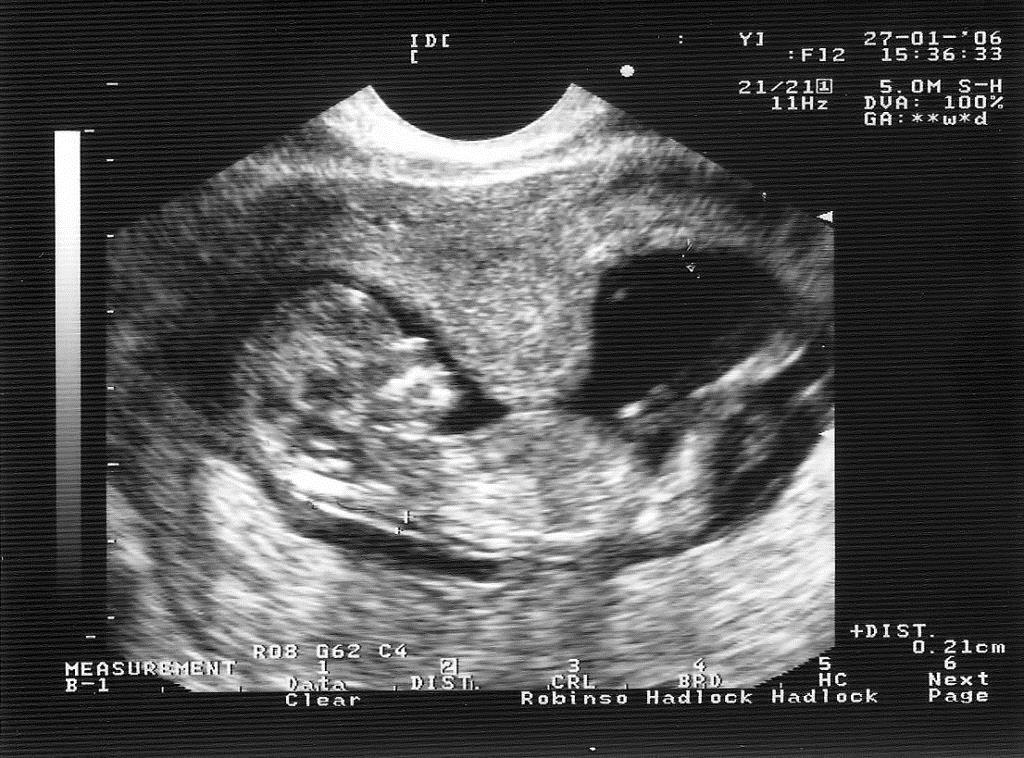

Для того, чтобы диагностировать гипертонус стенок матки, чаще всего применяется объективный осмотр беременной и ультразвуковое исследование. Кроме этого, врач назначает сдачу анализов крови с целью определить гормональный уровень. Касаемо лечения, оно базируется на обеспечении абсолютного покоя, приема спазмолитиков, седативных лекарственных препаратов и витаминов.

Как врачам удаётся определить тонус матки при беременности? Помимо самого распространённого метода пальпации, они прибегают к УЗИ-диагностике и кардиотокографии (КТГ).

При осмотре живота и влагалищном исследовании тонус матки легко определяется, на УЗИ видны напряженные мышечные волокна. Есть и специальный аппарат для измерения силы сокращения миометрия при беременности, хотя широкого применения он не получил – и без того симптомы состояния слишком заметны.